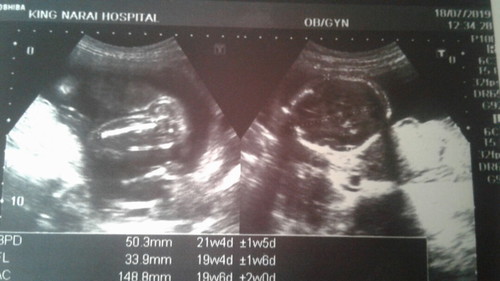

ในแผ่นอันตราซาวด์ไม่มีบอกนะคะ หรือแม่ถ่ายมาไม่ครบรึป่าว แต่ของแม่บ้านนี้ในใบอัลตราซาวด์ก็ไม่มีบอกเหมือนกันค่ะ บอกแค่ความยาวกระดูกแขน ขา ขนาดกระโหลกศรีษะ น้ำหนัก แล้วก็อายุครรภ์ค่ะ

ภาพซ้ายเป่นส่วนของขา แม่ลองสังเกตุดูดีๆน่ะ เหมือนมีลูกอัณฑะโผล่ออกมานิดนึง ถ้าให้เดาแม่ว่าได้น้องผช.ค้ะ ส่วนภาพขวานั้นเป็นส่วนของกะโหลกศรีษะค้ะ

นี้ค่ะที่แม่บอกว่า แม่แอบเห่นอันฑะน้อง แค่คาดเดาน้ะค้ะ